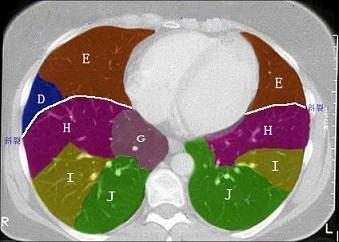

问题 结合肺段模式肺动脉干与右肺动脉层面、心室层面、主动脉弓层面、左右心房层面图(如图),选出左肺下叶的组成 ( )

选项 A.G+H+I+J B.F +H+I+J C.E+F+G+H+I+J D.D+E+F+G+H+I+J E.C+D+E+F+G+H+I+J

答案 B